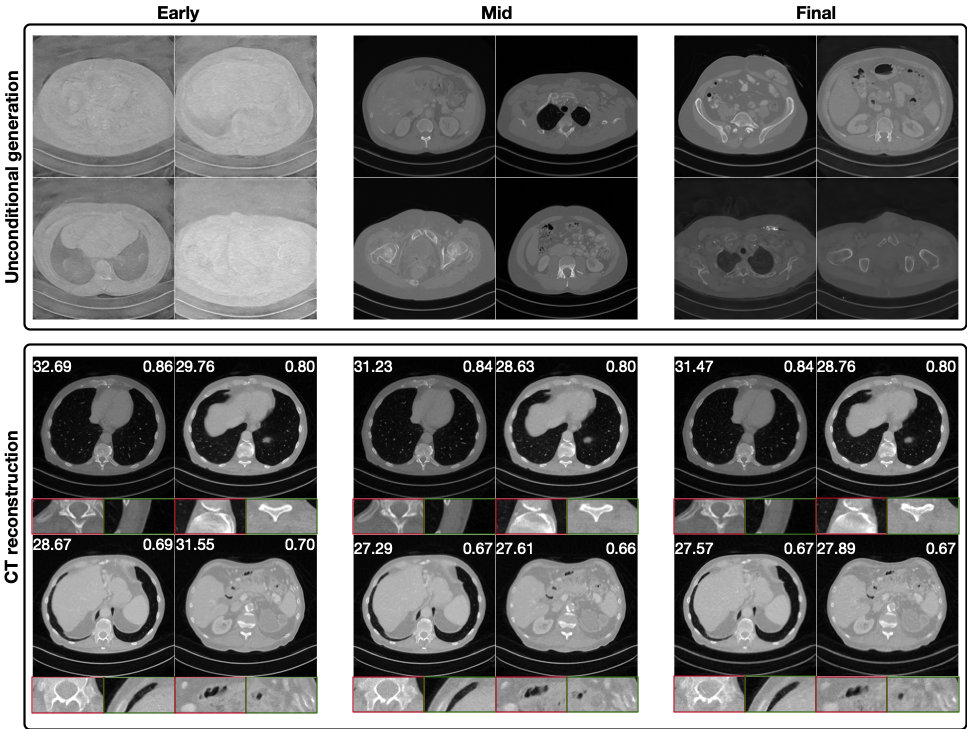

Refer to caption

Figure 2: Reconstruction results of diffusion-based and other established methods. Top: medical dataset (config iv, 80 angles with noise & ring artifacts); middle: industrial dataset (config ii, 20 angles with mild noise); bottom: real-world synchrotron dataset (60 angles). Red and green boxes show zoom-in regions. PSNR and SSIM appear in the top-left and top-right of each image. A dash (–) indicates that the method exceeded the 40 GB GPU memory limit for single-slice reconstruction and is therefore not executed. Images are consistently linear rescaled across methods to improve contrast.

Reconstruction Performance. As shown in Table 2, diffusion-based methods generally outperform classical and MBIR approaches in terms of PSNR and SSIM, but often fall short of fully supervised SwinIR. The INR-based approach achieves comparable metrics to diffusion methods, particularly in the noiseless scenario (config i) and on the real-world dataset. Visual examples in Figure 2 reveal that diffusion models tend to recover fine structural details that appear realistic but may diverge from the true reference, thereby reducing metric alignment. In contrast, INR and SwinIR produce smoother reconstructions, resulting in higher quantitative scores despite a loss of high-frequency details.

Among diffusion models, no single method or subclass (e.g., pixel vs. latent diffusion) consistently outperforms the others across all datasets and configurations, either visually or quantitatively. Performance on the real-world dataset is generally worse than on simulated data, likely due to factors such as limited training data quality and distribution shift. Perceptual metric LPIPS and full visual comparisons are discussed in Appendix A.14.